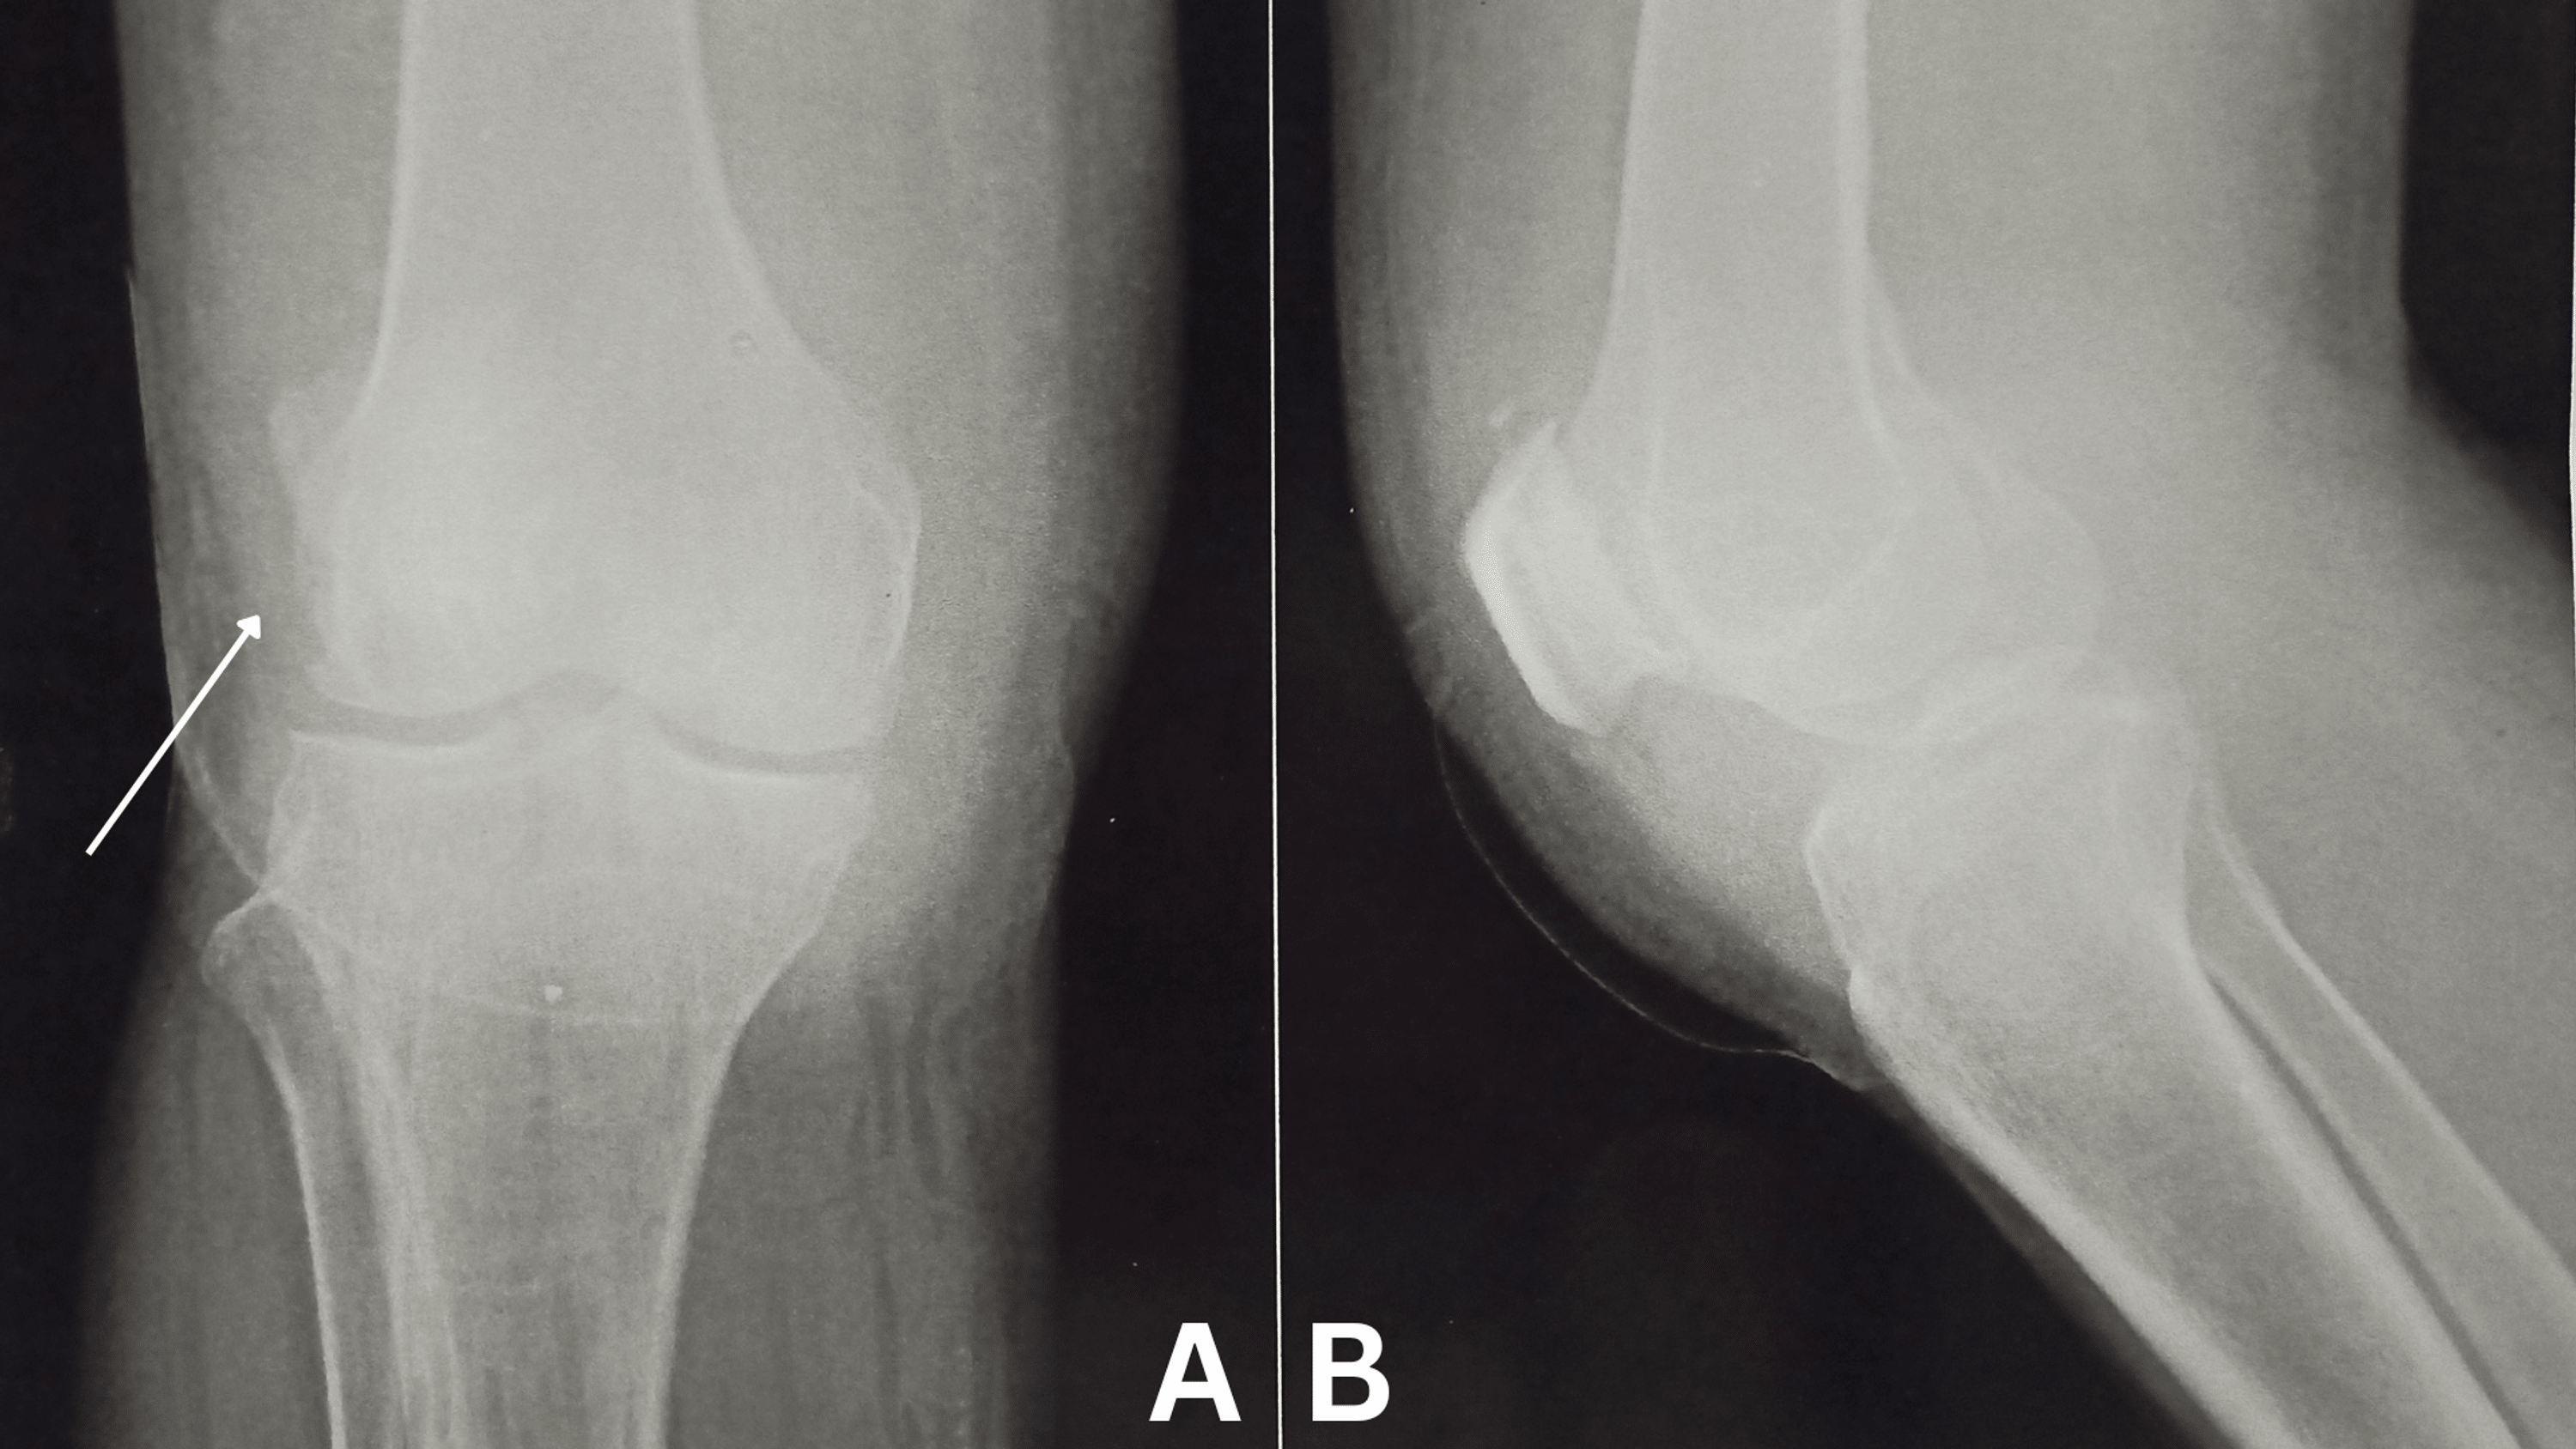

From www.researchgate.net

Limblength discrepancy and chondropathy after a septic arthritis of... Download Scientific Scraped Knee Sepsis native joint infections most commonly occur in the knee, followed by the hip, shoulder, ankle, elbow, and wrist. if the infection that caused your septic arthritis is not treated, the infection can spread to other parts of your body. septic bursitis occurs when a bursa becomes infected and inflamed. septic arthritis of the knee involves a. Scraped Knee Sepsis.